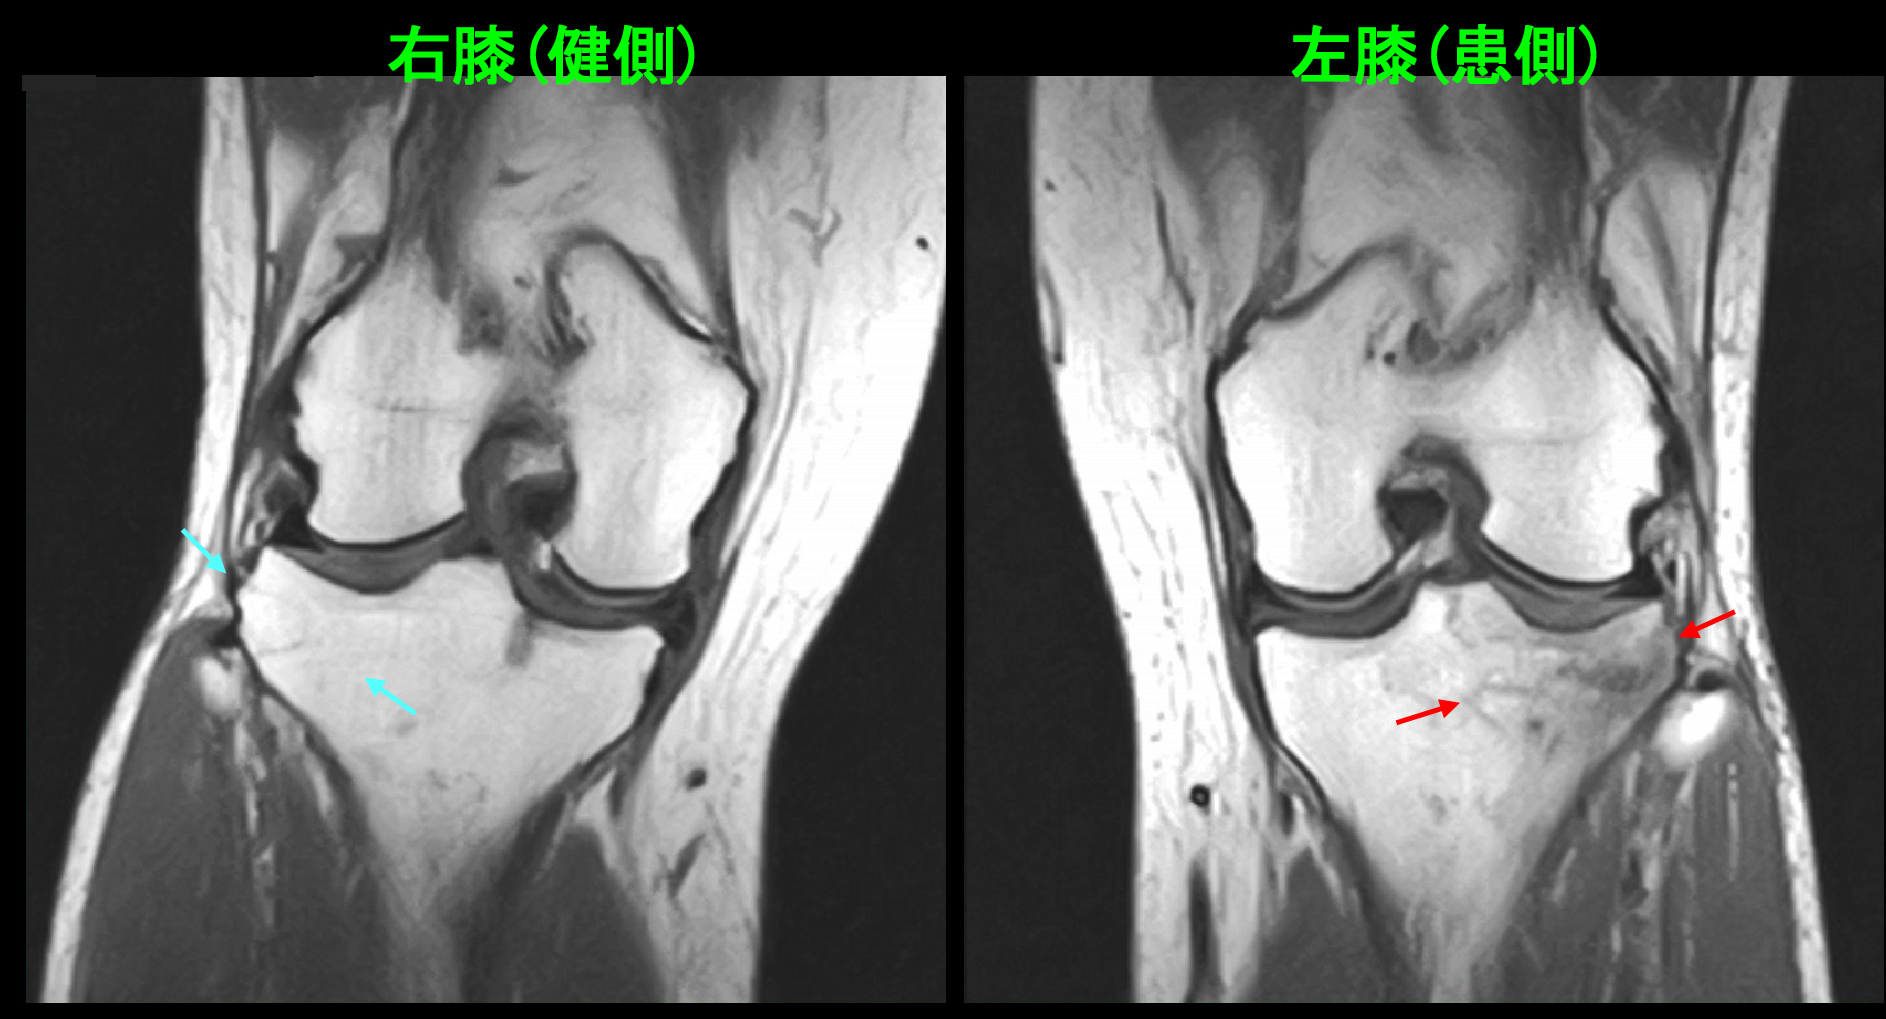

13才男 MR1.jpgMRI検査のSTIRという条件での冠状断(前後像)では確かに内側側副靭帯の周囲が白くなっており、同靭帯の炎症が認められました(赤矢印)が、それ以上に上腕骨の内側の筋付着部がより白くなっており、上腕三頭筋の損傷と診断しました(オレンジ矢印)。同部には内側側副靭帯よりも強い圧痛が確認されました。筋損傷の下側の骨内が少し白っぽくなっていますが(黄色丸領域)、大したことないと判断し、この程度の筋損傷・靭帯損傷に厳密な治療は迷惑であろうと考え、投薬のみを行いました。

しかし、その4日後の3月4日夜に左肘痛は増悪し、ほどんど眠れない状態となり、3月5日に再診されました。可動域は40度から45度とほとんど動かせません。躊躇せずMRIの再検査を行いました。

13才男 MR2.jpg

T1という条件の冠状断(前後像)で右肘上腕骨の外側関節部分の赤矢印が骨折線と判断されます。

13才男 MR3.jpg

違うT1の冠状断では上腕骨の内側部分(赤丸の領域)で骨が黒っぽく(低輝度と)なっていて、これも骨の損傷を示しています。初診時のSTIRの冠状断で上腕骨の内側部分(黄色丸領域)が白っぽかった(高輝度を呈していた)のはこの骨損傷に起因していたのです。